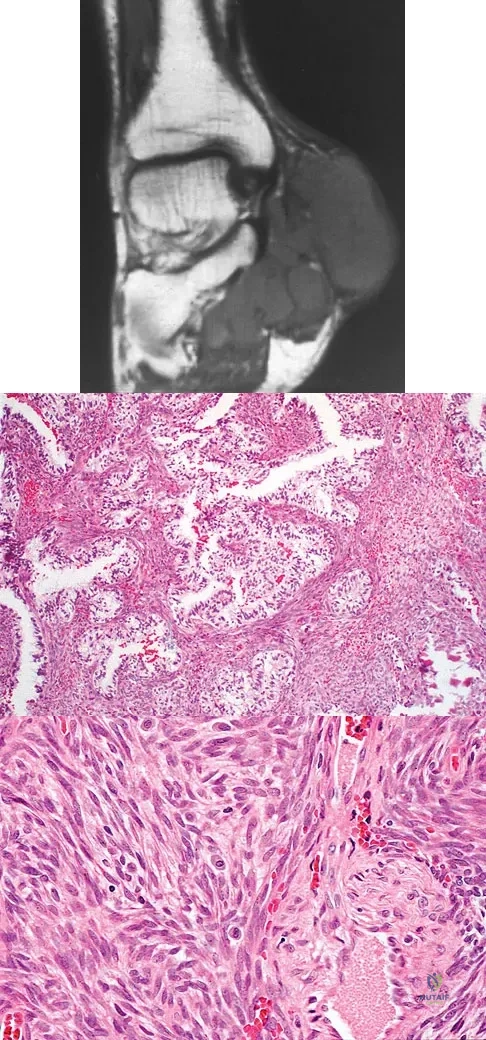

Question 49

An otherwise healthy 75-year-old man has a painful mass in the popliteal fossa of his right knee. A lateral radiograph of the knee, a CT scan of the distal femur, and a histopathologic specimen are shown in Figures 13a through 13c. Management should consist of

Explanation

Question 55

A 37-year-old man pulled his hamstring playing softball 3 weeks ago. The patient had not noted any mass prior to his injury. MRI scans of the posterior thigh are shown in Figures 4a and 4b. Figure 4c shows the biopsy specimen from a needle biopsy. What is the most likely diagnosis?

Explanation